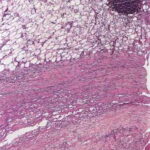

Histopathology

. A deep wedge biopsy to skeletal muscle including fascia is essential to making the diagnosis of eosinophilic fasciitis. The fascia is markedly thickened, appears homogeneous, and is permeated by a mononuclear inflammatory infiltrate . In some instances the infiltrate in the fascia contains an admixture of eosinophils . The underlying skeletal muscle in some cases shows myofiber degeneration, severe inflammation with a component of eosinophils, and focal scarring; in other cases, however, it is not involved.

In most cases the adipose tissue shows no significant changes, except that the fibrous septa separating deeply located fat lobules are thicker, paler staining, and more homogeneous and hyalinized than normal dermal connective tissue. In other cases, however, the collagen in the lower reticular dermis appears pale and homogeneous, and the entire subcutaneous fat is replaced by horizontally oriented, thick, homogeneous collagen containing only few fibroblasts and merging with the fascia